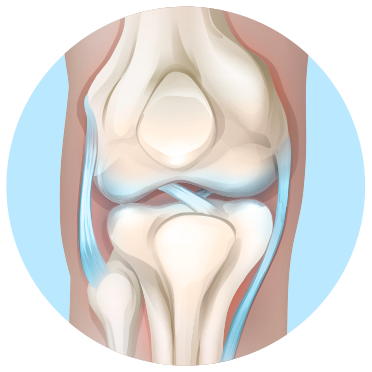

ЗДОРОВИЙ КОЛІННИЙ СУГЛОБ